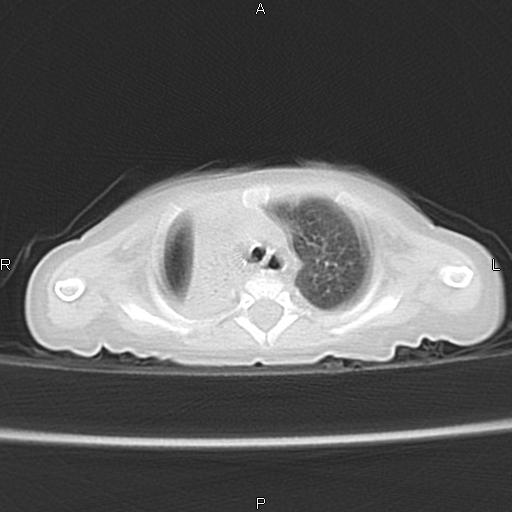

以下是引用aa13877358820在2010-7-26 12:35:00的发言:[br]男性,三个月,卧位胸片,咳嗽、气促、发热14天,两肺闻及细小水泡音。[br]

以下是引用jsdtd在2010-7-26 14:42:00的发言:[br]胸腺呈帆状,体位所致,没事。